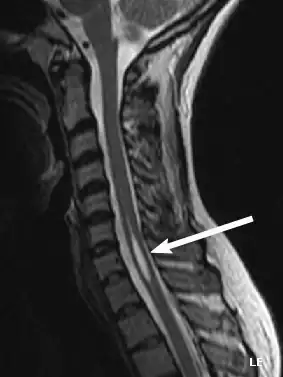

Diagnosis

Physicians now use magnetic resonance imaging (MRI) to diagnose syringomyelia. The MRI radiographer takes images of body anatomy, such as the brain and spinal cord, in vivid detail. This test will show the syrinx in the spine or any other conditions, such as the presence of a tumor. MRI is safe, painless, and informative and has greatly improved the diagnosis of syringomyelia.[14][15][16][17][18][19][20][21][22][23][24][25]

The possible causes are trauma, tumors, and congenital defects. It is most usually observed in the part of the spinal cord corresponding to the neck area. Symptoms are due to spinal cord damage and include pain, decreased sensation of touch, weakness, and loss of muscle tissue. The diagnosis is confirmed with a spinal CT, myelogram or MRI of the spinal cord. The cavity may be reduced by surgical decompression.